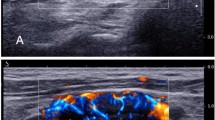

Quantification of the accumulation of DiR-labelled liposomes in the lymphostatic model. (a) Schematic diagram of the procedure used to establish an abdominal lymphedema model by resecting the ALN and ligating the lymphatic vessel toward the ALN. (b) Histological analysis showing development of lymph vessel hyperplasia in the lymphostatic model. (c) Quantification of fluorescent signals derived from DiR-labelled liposomes in the ILN and lymphostasis area.

To confirm abdominal wall lymphedema, histological analysis of abdominal skin tissue was performed. The presence of prominent fibrotic changes together with hyperplasia of lymph vessels in subdermal tissues indicated that the area between the ligation site and ILN was under a lymphedema status.

The fluorescence intensity in the lymphostasis region of interest (ROI) was increased temporarily and then decreased. This observation suggested that the lymphostasis might have triggered the formation of a new collateral route (Fig. 6c).